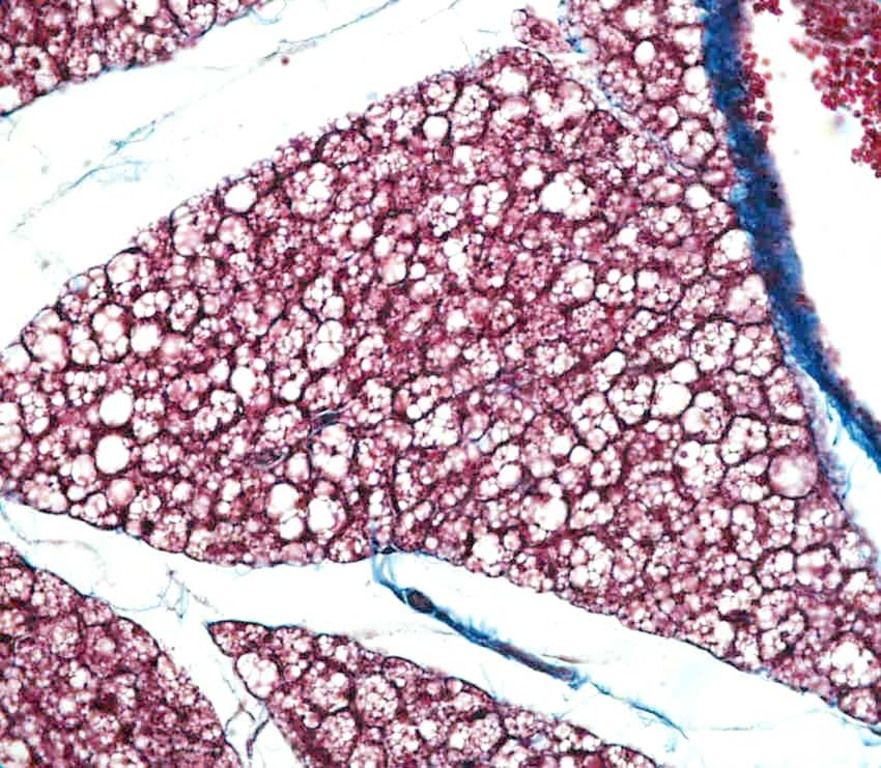

Question

Identifiez le type de tissu conjonctif (en h à g) ainsi que les structures pointées (en b à g petite structure foncée ronde), et la coupe dans-laquelle on se trouve :

Answer

• tissu adipeux jeune ou graisse brune

• gouttelette lipidique

• noyau adipocyte

• trachée - thyroïde